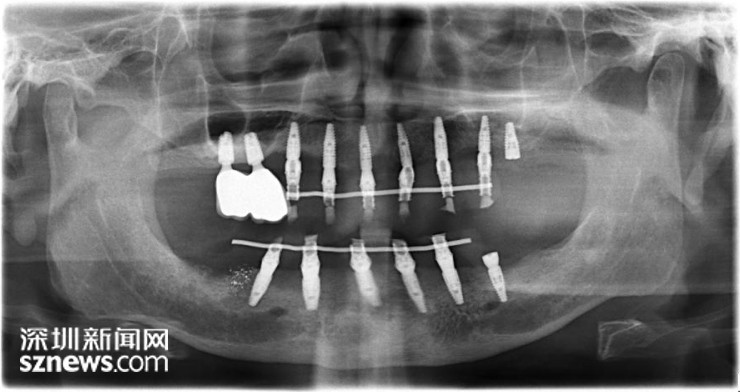

胡老伯术后口内拍片照

在拔完牙后三个月,胡老伯如约来到远东找到黄教授为他制定了细致周密的全口种植即刻修复手术计划:胡老伯需植入13颗种植体。考虑到此次手术工作量大、难度大、时间长且胡老伯已72岁高龄。术前,远东黄教授通过动态导航设计软件,对植入位置、植体型号等问题进行充分沟通,模拟种植体植入的位置、角度、深度,避开下颌神经线,保障手术顺利。

深圳远东妇产医院黄教授通过数字化工具,拍摄CBCT,为他做了口内检查,发现胡老伯因重度牙周炎致使口内的20多颗自然牙全部松动,且无保留价值。建议胡老伯先拔除口内所有患牙后再进行全口牙种植修复。